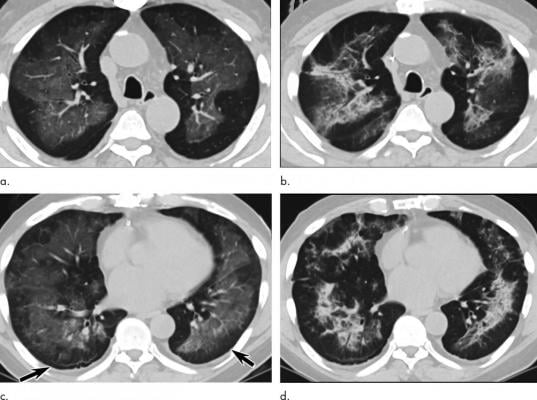

Electronic cigarette or vaping product use-associated lung injury in a 51-year-old man manifesting as an acute lung injury pattern at CT with subsequent organization. (a, c) Axial unenhanced CT images at presentation through (a) mid and (c) lower lungs show ground-glass opacity with subpleural sparing (arrows); this distribution was present in 45% of chest CT studies at presentation in our cohort (11). (b, d) Axial unenhanced CT images obtained 6 days later show ground-glass opacity has transitioned to consolidation and mild architectural distortion, consistent with developing organization. The patient was initially treated with antibiotics followed by corticosteroid therapy, with slow clinical improvement. Image courtesy of Radiological Society of North America

Mayo Clinic radiologist Michael B. Gotway, M.D., recently expanded on that study by looking for patterns on chest CT scans that might correlate with the previously observed pathological findings. The study included 26 patients who met the EVALI criteria and had undergone CT and biopsy or some other type of tissue removal. Gotway and colleagues classified the CT scan pattern according to several different recognized patterns. One pattern is ground glass opacity, an area on the CT scan that appears whiter than normal but does not obscure the underlying structure of the lung. Another is consolidation, or denser white areas on CT.

“We read the CT scan and then plugged it into one of those patterns and correlated that with histopathology,” Gotway said. “What we found out was that ground glass opacity, sometimes with consolidation, is by far the most common pattern that we see with EVALI.”

The researchers found some good news in their study, as it appears that signs of EVALI on imaging may resolve quickly with cessation of use of the offending agent, often supplemented by corticosteroid therapy.